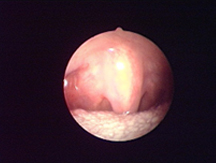

適于精確損毀破壞內(nèi)部組織。

適合于精準的點狀凝血。

適合于在重要的部位實現(xiàn)凝血。